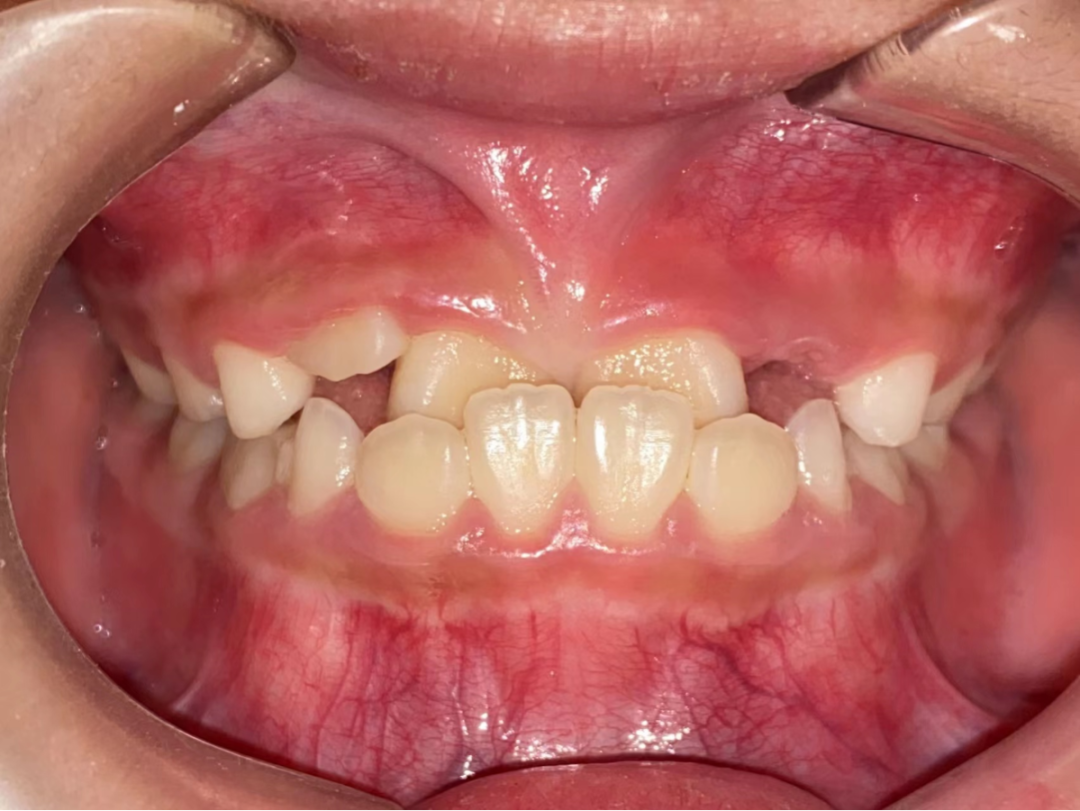

什么是错颌畸形?

错颌畸形是指在生长发育过程中,由先天的遗传因素或后天的环境因素,如疾病、口腔不良习惯、牙齿替换异常等各种原因导致的牙齿、颌骨、颅面的畸形。包括牙齿排列不齐、上下牙咬合关系错乱、颌骨大小或形态异常以及面部畸形等。错颌畸形不仅影响外貌,而且也影响功能。

错颌畸形的危害有哪些?

1、影响颅颌面发育:在儿童生长发育过程中,错颌畸形如不及时治疗,就会影响儿童口腔及面部软硬组织的正常发育。例如下牙列位于上牙列外侧,就会妨碍上牙列和上颌骨向前正常发育,导致面中部发育不足,即地包天。

乳牙早失导致拥挤

间隙保持器为“新牙”萌出保留空间

2、阻断矫治。当错颌畸形发生的早期,通过简单的方法进行早期矫治,阻断错颌畸形的发展,并引导面部向正常发育方向发展,常称阻断矫治。如早期前牙拥挤(牙弓缩窄等)使用扩弓矫治器矫治,早期牙源性前牙反合使用简单合垫舌簧矫正器矫治。

儿童错合畸形早期矫治是阻断影响儿童颌骨、牙齿正常发育的因素,促进颌面部正常发育,降低II期矫正的难度,减少II期矫正的时间,甚至不需要II期矫正。让孩子早期获得自信,绽放灿烂笑容。

术前→术后